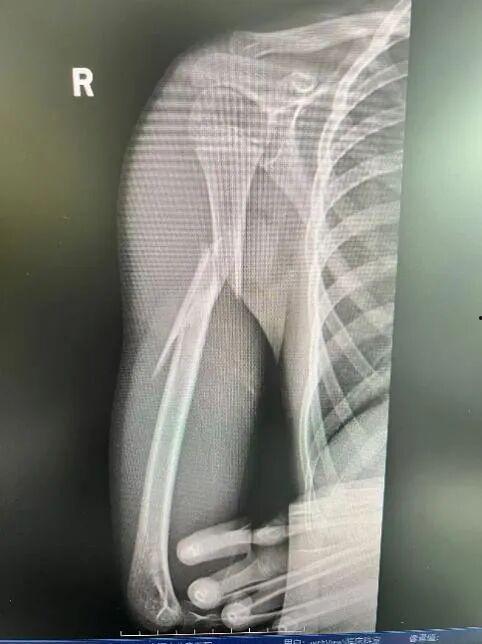

3. 形状改变:上臂的形状可能会发生改变,比如变短或弯曲。

4. 功能受限:上臂的活动能力会受到影响,比如抬不起来。